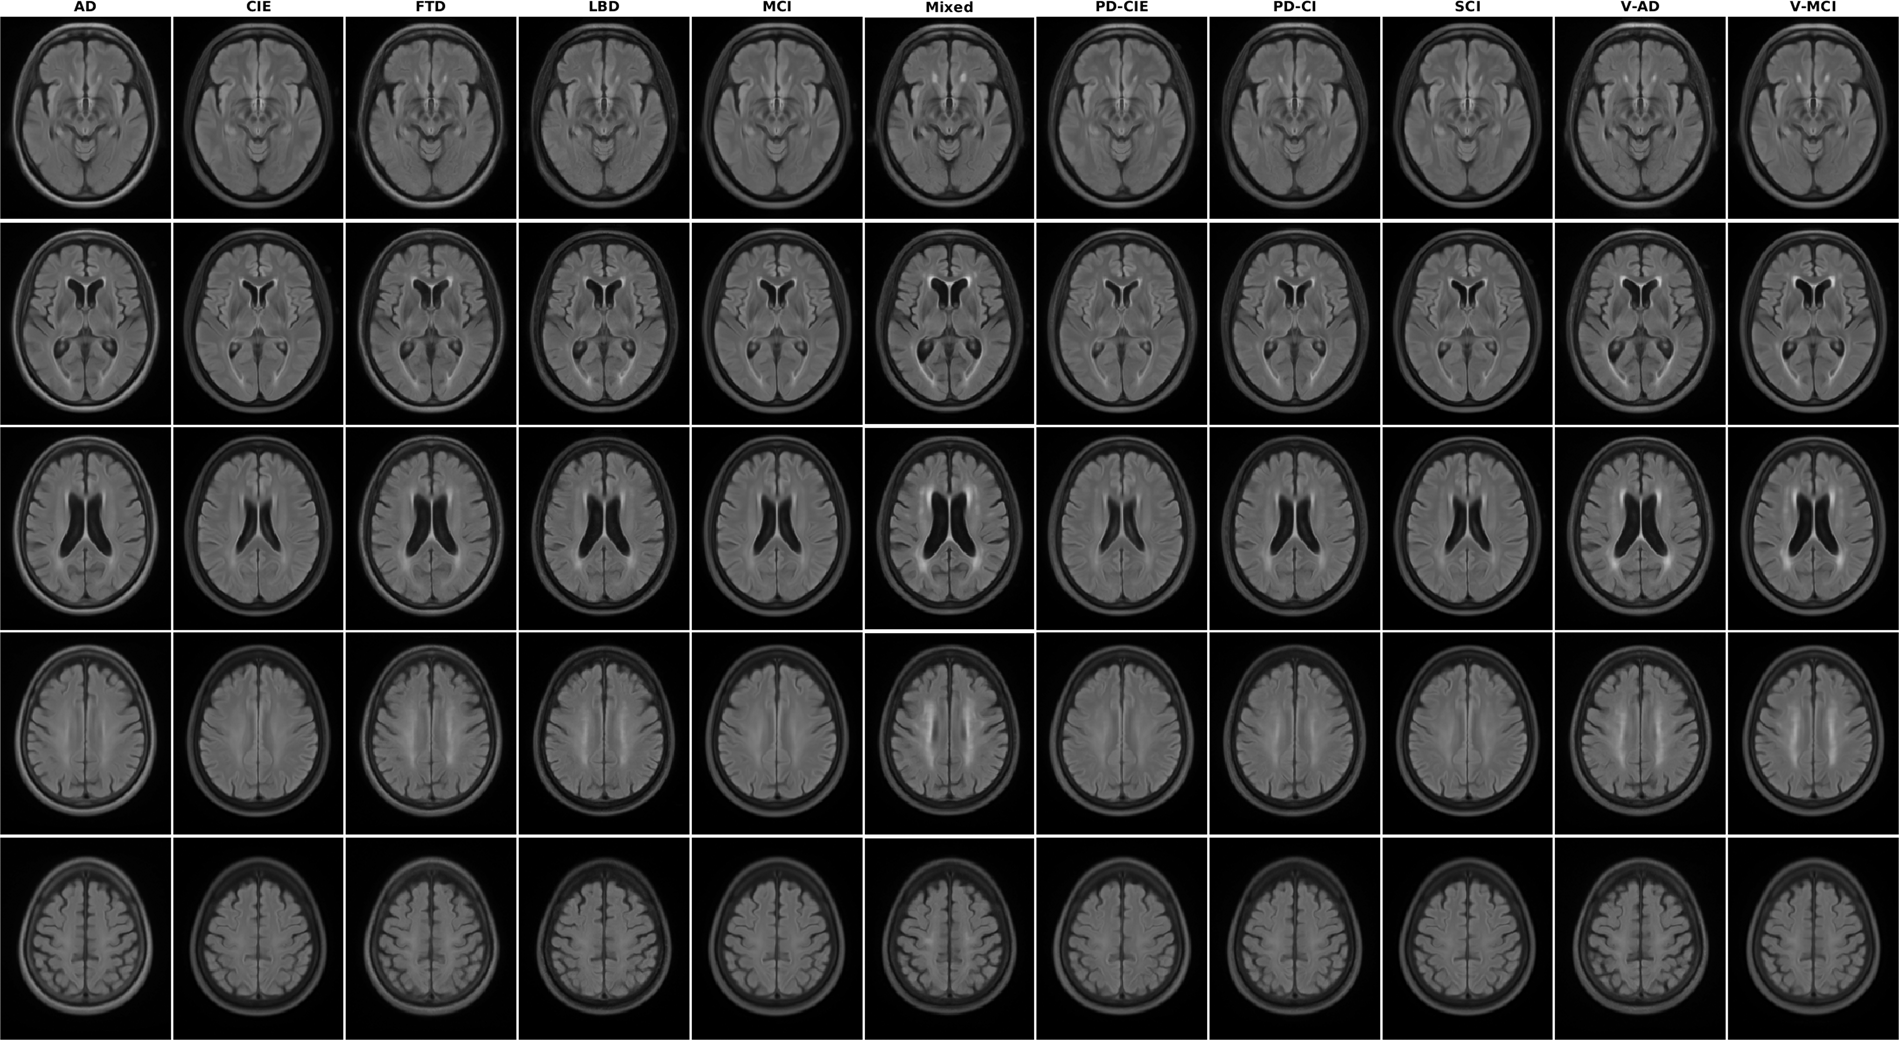

Axial slices of FLAIR average templates for all diagnostic groups.